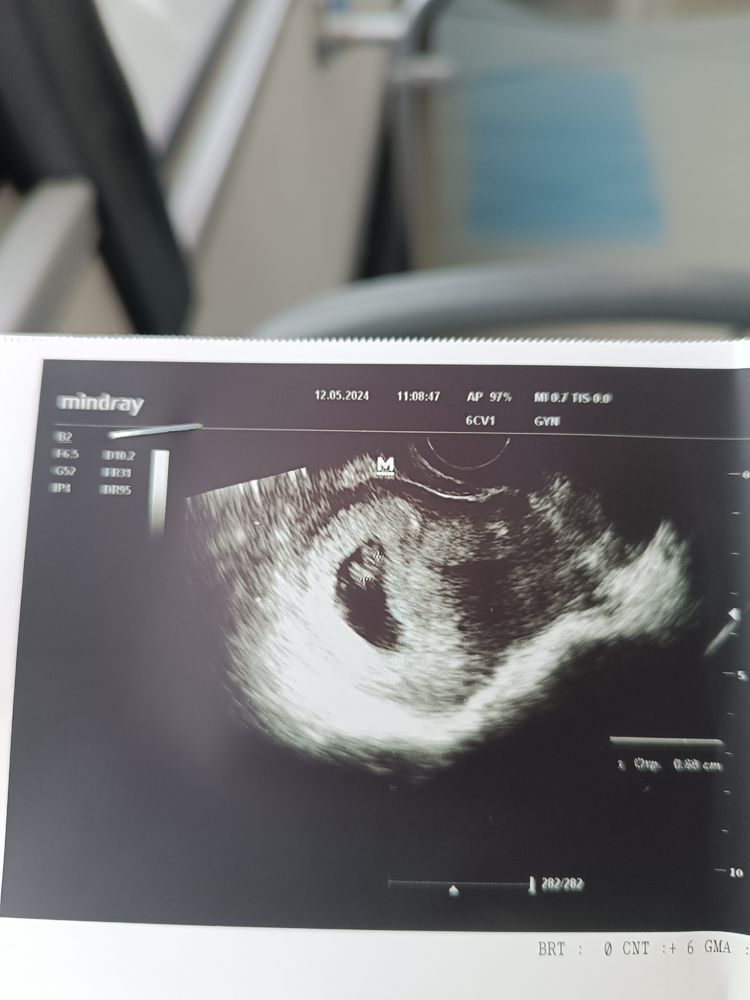

Первое УЗИ 7 недель+ 2 дня

Ну вот наше первое УЗИ. Врач остался очень доволен. Сказал все просто отлично. Но меня смущает ктр-6,3 мм. По таблицам маловато. Теперь переживаю.

Может конечно и погрешность, потому что аппарат так себе у нее...Ещё и срок поставила 6,3 Эмбриональных! недель. Кто делал УЗИ на таком сроке?